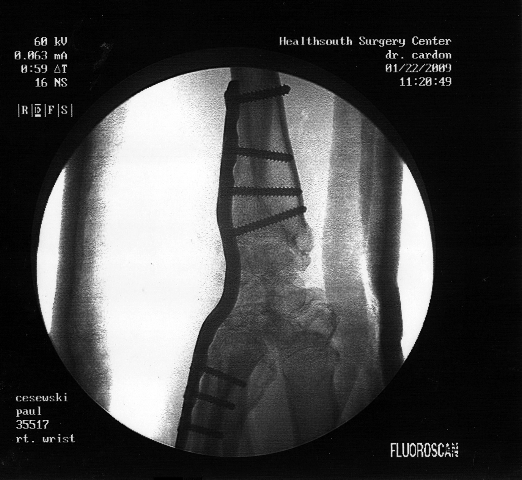

WHY: Paul ‘da Plumber’ had major surgery on his right wrist, has it in traction, and will be out of work and unable to use it for several months. Paul — as you probably know — builds amazing bike powered rides and sculptures, and all sorts of silly devices.

One inch of the ulna was removed, ground up and packed into the small bones in the back of the hand to reinforce the hand. A permanent metal sheathe was put into the wrist about the size of a butter knife and attached to the bones of hands and wrist with 7 surprising large full size bolts. They did a bunch of other things to his wrist that will hopefully minimize the constant pain he has experienced for years. Post Op photos: